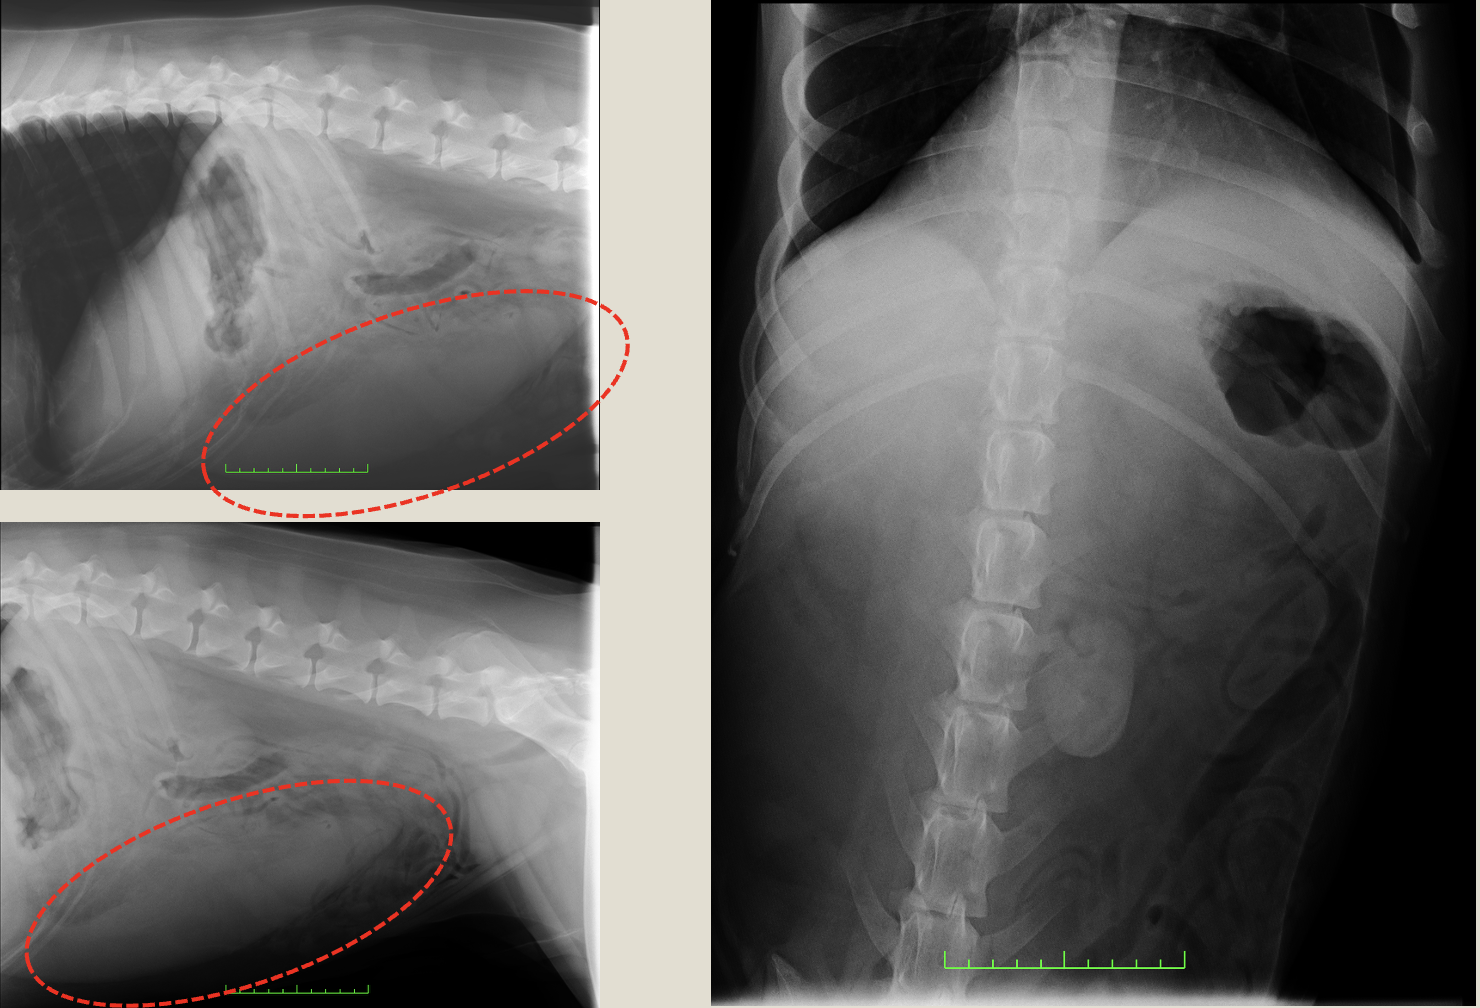

レントゲンより、腹腔内に腫瘤陰影

before